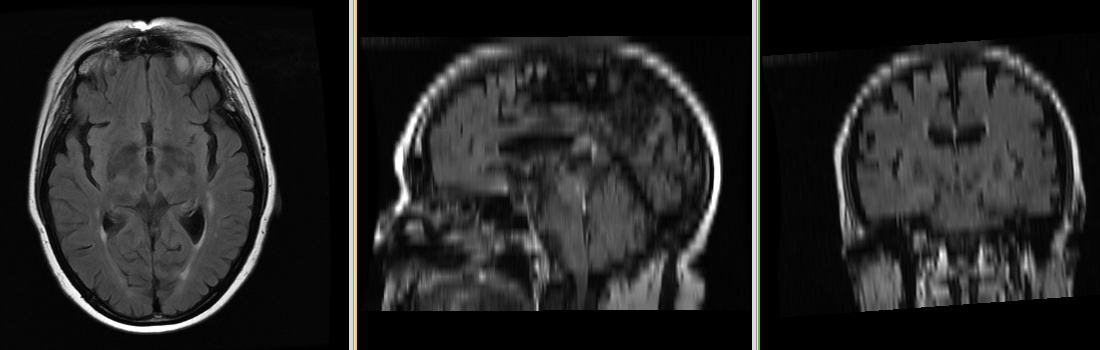

Single channel automatic segmentation of T1 and T2 MRI brain scans into the major tissue classes (gray matter, white matter, csf). The task can be applied to T1 and T2 brain scan showing parts of the skull and neck. The pipeline consist of the following steps:

Image Dimension = 512 x 512 x 26

Image Spacing = 0.4688 x 0.4688 x 6